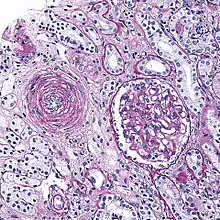

Hyaline arteriolosclerosis

Also arterial hyalinosis and arteriolar hyalinosis refers to thickening of the walls of arterioles by the deposits that appear as homogeneous pink hyaline material in routine staining.[3] It is a type of arteriolosclerosis, which refers to thickening of the arteriolar wall and is part of the aging process.[4]

Hyperplastic arteriolosclerosis

This is a type of arteriolosclerosis involving a narrowed lumen.[4] The term "onion-skin" is sometimes used to describe this form of blood vessel[8] with thickened concentric smooth muscle cell layer and thickened, duplicated basement membrane. In malignant hypertension these hyperplastic changes are often accompanied by fibrinoid necrosis of the arterial intima and media. These changes are most prominent in the kidney and can lead to ischemia and acute kidney failure.